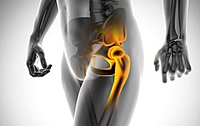

고관절은 골반을 지탱하는 중요한 관절로, 근육과 힘줄로 구성되어 있습니다. 학계에서는 이를 엉덩이 관절이라고 부르며, 신체의 하중을 지탱하는 중요한 역할을 합니다. 고관절은 우리가 정상적으로 서고 움직일 수 있도록 도와주며, 달리기, 점프, 무거운 물건을 들 때 최대 체중의 2~10배에 달하는 압력을 견딥니다. 따라서 적절한 관리가 필요합니다. 오늘은 고관절에서 나타날 수 있는 고관절 통증 증상 10가지에 대해 알아보겠습니다.

고관절 통증의 주요 원인은 퇴행성 질환으로, 나이가 들면서 관절 손상이 발생하는 것입니다. 고관절 자체의 구조적 문제, 주변 근육과 인대의 문제, 척추와 골반 문제 등 다양한 원인이 있습니다. 퇴행성 고관절염, 대퇴골두 무혈성 괴사, 대퇴골 경부 골절, 퇴행성 관절염, 급성 활액막염 등이 주요 원인입니다. 이러한 질환들은 심각한 합병증을 유발할 수 있어 빠른 치료가 필요합니다.